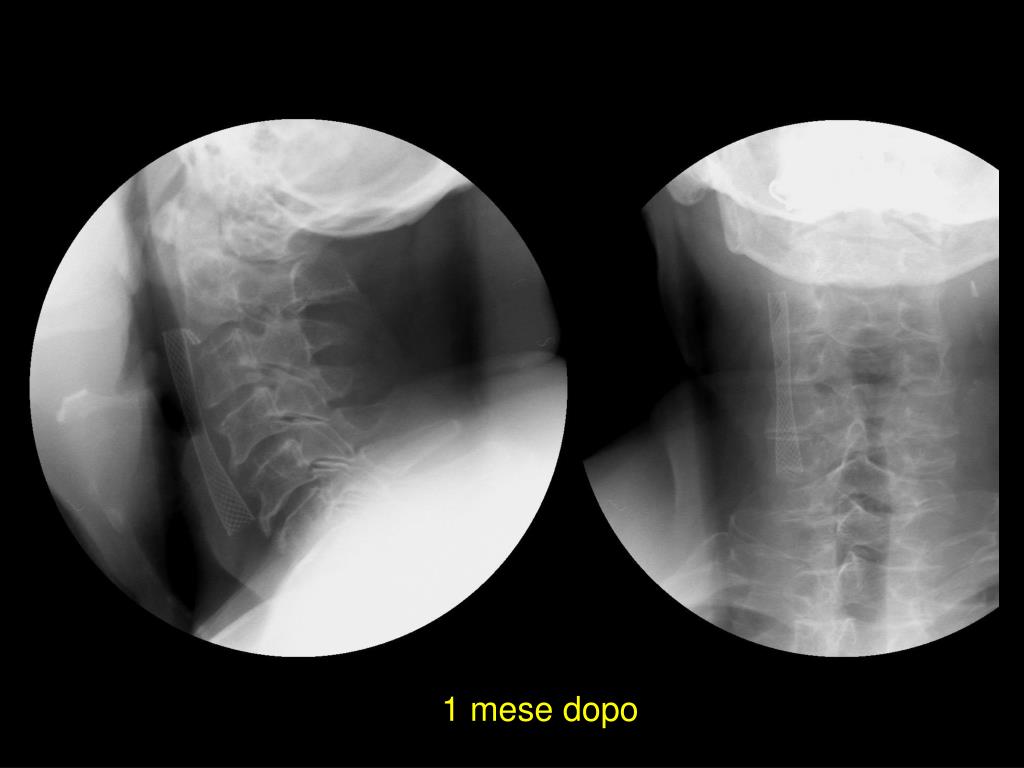

27. 1 mese dopo

28. Caso stenting bilaterale CI destra